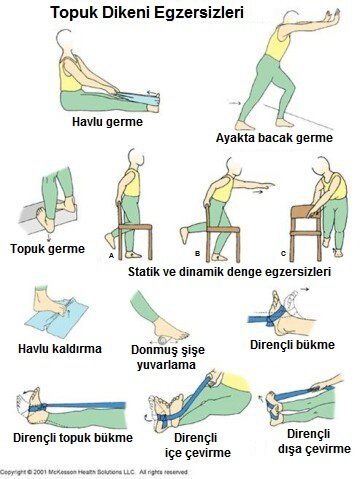

Topuk dikeni hastalığında en önemli sebep şişmanlıktır. Ancak hastalık, normal kilolu kişilerde de görülebilir. Özellikle çocukluk ve gençlik yıllarında ayak sağlığına önem vermemiş ve genellikle doğru ayakkabı tercihi yapmamış kişilerde, uzun süre ayakta kalmayı gerektiren işlerde çalışanlarda, ayağında yapısal bozukluk olanlarda (Düztabanlık, ayak tabanı yüksekliği), yürüme bozukluğu olan kişilerde ve bazı romatizmal hastalıklarda daha sık görülür. Topuk dikeni tedavisinde çeşitli yöntemler vardır. Aşırı kilolu kişilerin öncelikle kilo vermesi sağlanmalıdır. Kullanılan ayakkabılarda düzenleme yapılmalıdır. Özellikle yumuşak tabanlı, topuk kısmı darbe emen ayakkabılar tercih edilmelidir. Ayakkabı veya evde kullanılan terliklerin içine yerleştirilen, ağrılı bölgeye gelen kısmı delik olan topuk yastıkçığı/ taban desteği kullanılması önerilir. Ayak tabanını esnetecek egzersizler önerilir ve gün içinde birkaç kez tekrarlanmalıdır. Ağrı kesiciler de tedaviye eklenebilir. Ayrıca ağrılı bölgeye her gün birkaç dakika yapılacak masaj da etkili olabilir. Tüm bunlara rağmen ağrı giderilemezse, topuğa kortizon enjekte edilebilir. Ancak kortizon ağrıyı ortadan kaldırsa da, uygulama şekli aşırı ağrılı olduğu için hastalar tarafından zor tolere edilir. Ayrıca kortizonun topuk yağ yastığında bozulmaya yol açma riski de vardır.

Sorunun çözümünde genellikle ayakta fazla kalmama, ayakkabı tabanında destek kullanımı, fizik-tedavi egzersizleri gibi tedaviler kullanılmakla birlikte çok ileri vakalarda biyolojik tedaviler veya cerrahi müdahale ile problem ortadan kaldırlmaktadır.

Topuk Dikeni Egzersiz Hareketleri Nelerdir.

topuk-dikeni-egzersizleri